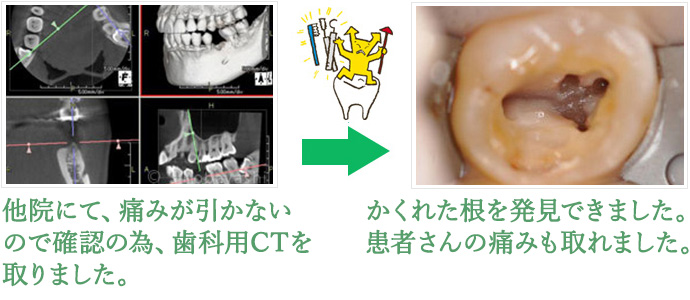

根管治療

~歯の根の治療は精密に行います~

細菌に感染した歯質や神経の除去を徹底的に行うことで、歯の根の病気を治療・予防するのが根管治療です。

細菌を取り除くことができなかった状態でクラウンを被せたり、詰め物を詰めると、細菌が発生した場所から後になって痛みが生じる場合があり、そのようなケースで用いられるのが歯の根の治療、いわゆる根幹治療なのです。

通院が平均で5回必要という根気のいる治療法ですが、急ぐことで細菌を全て除去しきれなかったとなると細菌が拡大、増殖してしまい、また再発するという悪循環のサイクルに陥ることも考えられます。そのため、当院では必要な場合は最新のCTを使用するなどして、細かい根管がないか確認していきます。

神経を取った歯なのに痛みがあるのはなぜ?

歯の神経を取ったとしても、何らかの原因によって歯の根部分が炎症を起こすと痛みが出る場合があります。炎症の原因を取り除く治療を行いましょう。